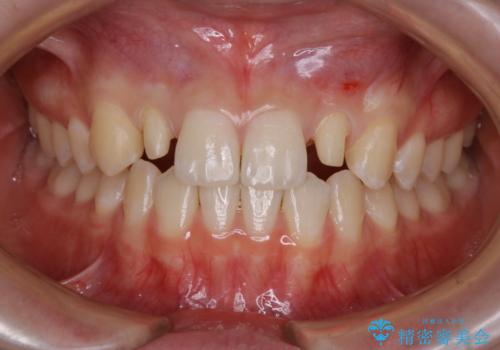

- 初診時、前歯部の見た目の改善を主訴にご来院されました。生まれつき歯が小さい状態の「矮小歯」とそれに伴う正中の「すきっ歯」があるため、大きなガタつきはないものの笑った時の印象に違和感が出る状態となっていました。

矮小歯が傾斜していることなどを踏まえ、より安全に治療を進めるために部分矯正を併用したセラミッククラウンでの治療を行うこととなりました。

前歯や小臼歯では、生えてくる歯が小さく審美的に影響が出る場合があります。このような歯を矮小歯(わいしょうし)と言います。

今回のケースでは、歯が小さいだけでなく傾斜もしていたため補綴治療時に歯を削ることで神経の症状が出る可能性がありました。そのため、事前に部分矯正を行い歯軸の改善を行っておくことで、歯髄を温存することができました。